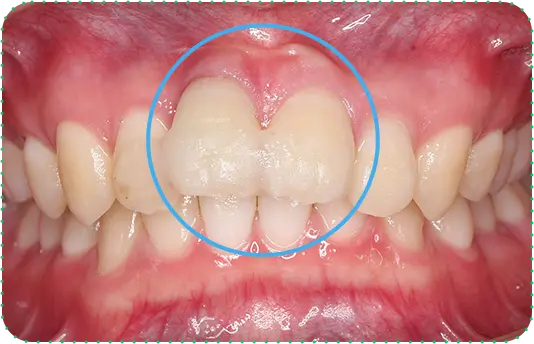

Before

After

主訴

上の前歯が抜けそう

治療期間

6か月

治療費

30万円

治療内容

右上1番を抜歯後に骨と歯茎を増やし、隣の歯の裏側を少量削り、接着性ブリッジにて修復

治療のリスク

咬み合わせによっては、セラミックが欠ける可能性があります。